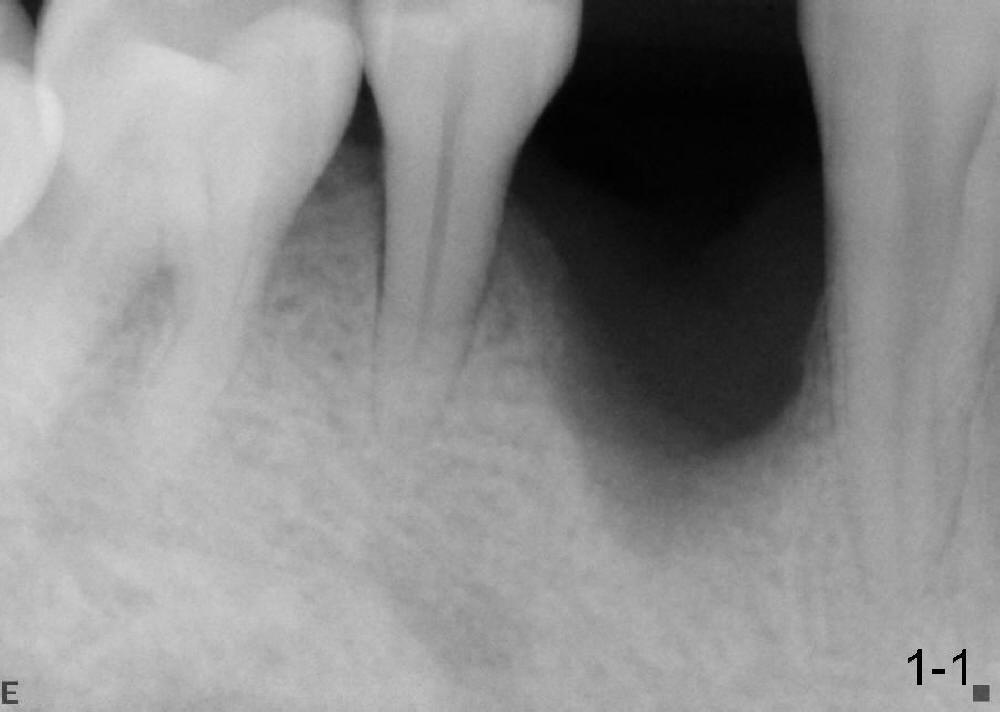

沐旭升医师送来两例植骨病例:第一例使用金属网(图一);第二例上颌骨头高度3.4 mm (CT 显示),上颌窦提高术植骨(侧面进路),同期植牙(图二)。打开每张图看评论。

Case1 is bone graft with metal mesh. Case 2 is bone graft with sinus lift through window, since the  existing bone only has 3.4 mm in the CT film (英文部分由沐医生提供).